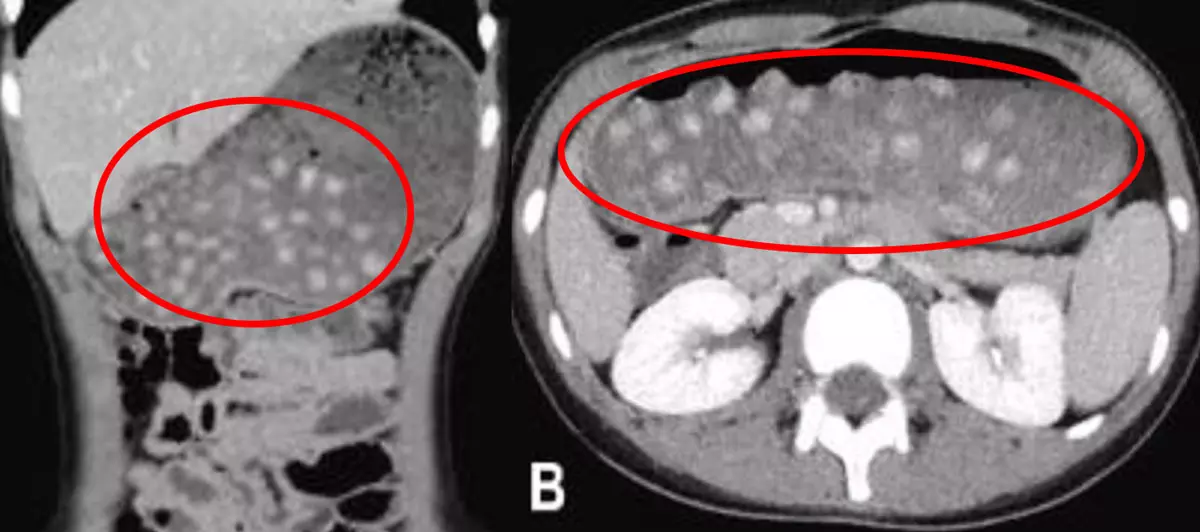

일본 시즈오카현 후지시 종합병원 소아과 의료진에 따르면, 기저질환이 없는 10세 영아가 상복부 통증을 호소하며 내원했다. 복부 CT 검사 결과, 위 내에 다수의 진주 모양 덩어리들이 관찰됐다. 크기는 8~10mm 정도였다.

그는 내원 6시간 전 버블티를 섭취했었다고 전했고, 위를 막고 있던 덩어리들의 정체는 버블티 속에 들어 있는 타피오카 펄이었다. 이에 의료진은 코로 가느다란 관을 넣어 위의 압력을 낮춰주는 비위관 감압술을 시행했다. 이후 추적 관찰 검사에서 위 내 병변들이 십이지장으로 배출된 뒤 소장으로 이동한 것이 확인됐다.